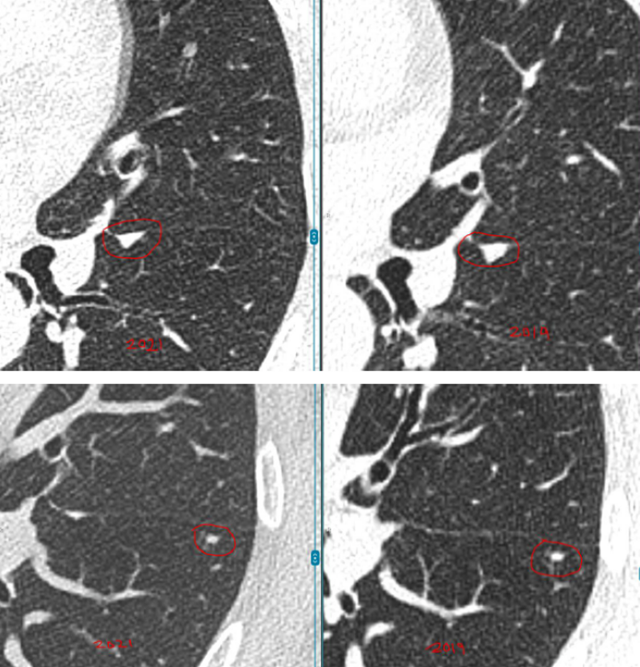

具体来看,右肺有一个磨玻璃结节(约4mm),左肺还有两个实性结节(约5mm、3mm)。

之后的4年里,这3枚小结节都没有什么变化,这让她逐渐放下心来。

然而在随后的一次复查中,CT结果显示磨玻璃结节“密度略微增加”,而且又新出现了一枚3mm的小结节。

“先看左肺这两枚实性结节,它们在这几年一直很稳定,没有明显增大,形态也没有变化。像这类稳定超过3年的小实性结节,良性可能性超过了99%。从片子上看,它们更像是肺部之前因为旧损伤留下的痕迹。”L教授说。

关于右肺的4mm磨玻璃结节,L教授对比了新旧影像,并不认为它在恶化。

“这一枚,是您现在担心的,对吗?因为报告里提到它的密度比以前稍微高了一点。但从影像上看,这种变化还是非常轻微的,目前还没有达到让我们怀疑它正在明显恶化的程度。它确实值得继续随访,但至少以现在这个状态,还谈不上需要立刻处理,更不意味着已经朝着癌的方向快速发展。”L教授说。

关于右肺新出现的那枚大约3mm的磨玻璃结节,L教授同样为林女士进行了详细解释。

“像这么小、这么淡的磨玻璃结节,在临床上很常见,很多时候更像是一过性的炎性反应,可能和轻微感染甚至短期肺部状态变化有关。有些结节过一段时间复查,自己就消失了。所以对这枚结节,我目前更倾向于把它看作一个温和的、需要观察的信号,而不是一个必须马上干预的问题。”L教授说。

L教授总结道:“总体来看,您现在这4枚结节都还很小,而且没有哪一枚表现出必须马上手术或活检的证据。左肺两枚实性结节长期稳定,右肺原有的磨玻璃结节虽然密度略有变化,但幅度很小,新发的3mm磨玻璃结节也更像炎性改变。换句话说,它们都还没有到‘该切的时候’。现阶段继续按计划随访,是安全的,也是更合理的做法。”